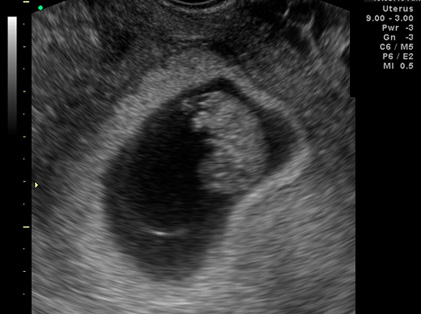

임신 초기 초음파 영상 사진 (출처 : 대한초음파의학회)

시기에 따라 초음파를 통해 확인하는 항목이 달라요! 임신 초기에는 질 내 초음파로 자궁 안 태낭 (태아가 들어있는 주머니) 또는 태아 심박 여부를 확인했었죠? 임신 8-10주에는 CRL (태아의 머리부터 엉덩이까지 길이) 측정을 통해 임신 주수를 확정해요. 이시기의 아이는 CRL에 개인차가 없거든요! 장신의 농구선수도, 귀여운 체조선수도 CRL 수치는 비슷비슷! 성별을 알려주는 것도 이 초음파예요!